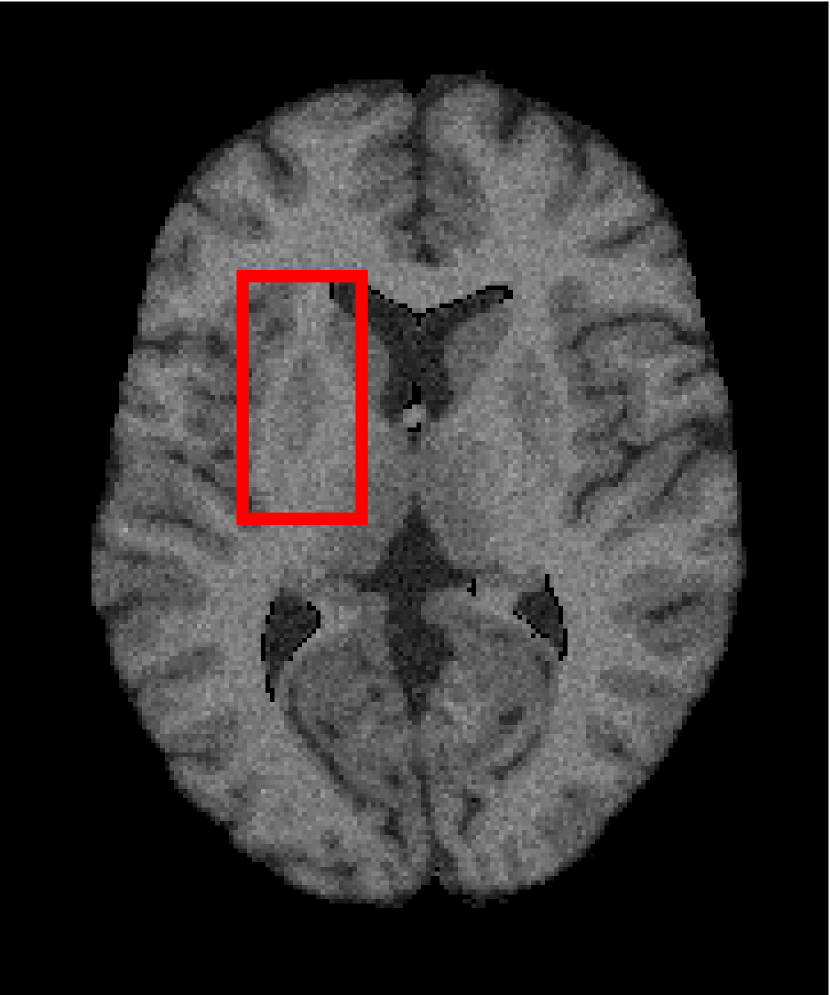

Next, we representatively segment five medical images from BrianWeb. They are represented as five slices in the axial plane with a sequence of 70, 80, 90, 100 and 110, which are generated by T1 modality with slice thickness of 1mm resolution, 9% noise and 20% intensity non-uniformity. Here, we set c=4𝑐4c=4 for all cases. The comparison between WRFCM and its peers are shown in Fig. 9 and Table II. The best values are in bold.

Figure 9: Segmentation results on five medical images. The parameter: ϕ=5.35italic-ϕ5.35\phi=5.35. From top to bottom: noisy images, ground truth, and results of FCM_S1, FCM_S2, FLICM, KWFLICM, FRFCM, WFCM, DSFCM_N, and WRFCM.

By a view of the marked red square in Fig. 9, we find that FCM_S1, FCM_S2, FLICM, KWFLICM and DSFCM_N are vulnerable to noise and intensity non-uniformity. They give rise to the change of topological shapes to some extent. Unlike them, FRFCM and WFCM achieve sufficient noise removal. However, they produce overly smooth contours. Compared with its seven peers, WRFCM can not only suppress noise adequately but also acquire accurate contours. Moreover, it yields the visual result closer to ground truth than its peers. As Table II shows, WRFCM obtains optimal SA, SDS and MCC results for all five medical images. As a conclusion, it outperforms its peers visually and quantitatively.